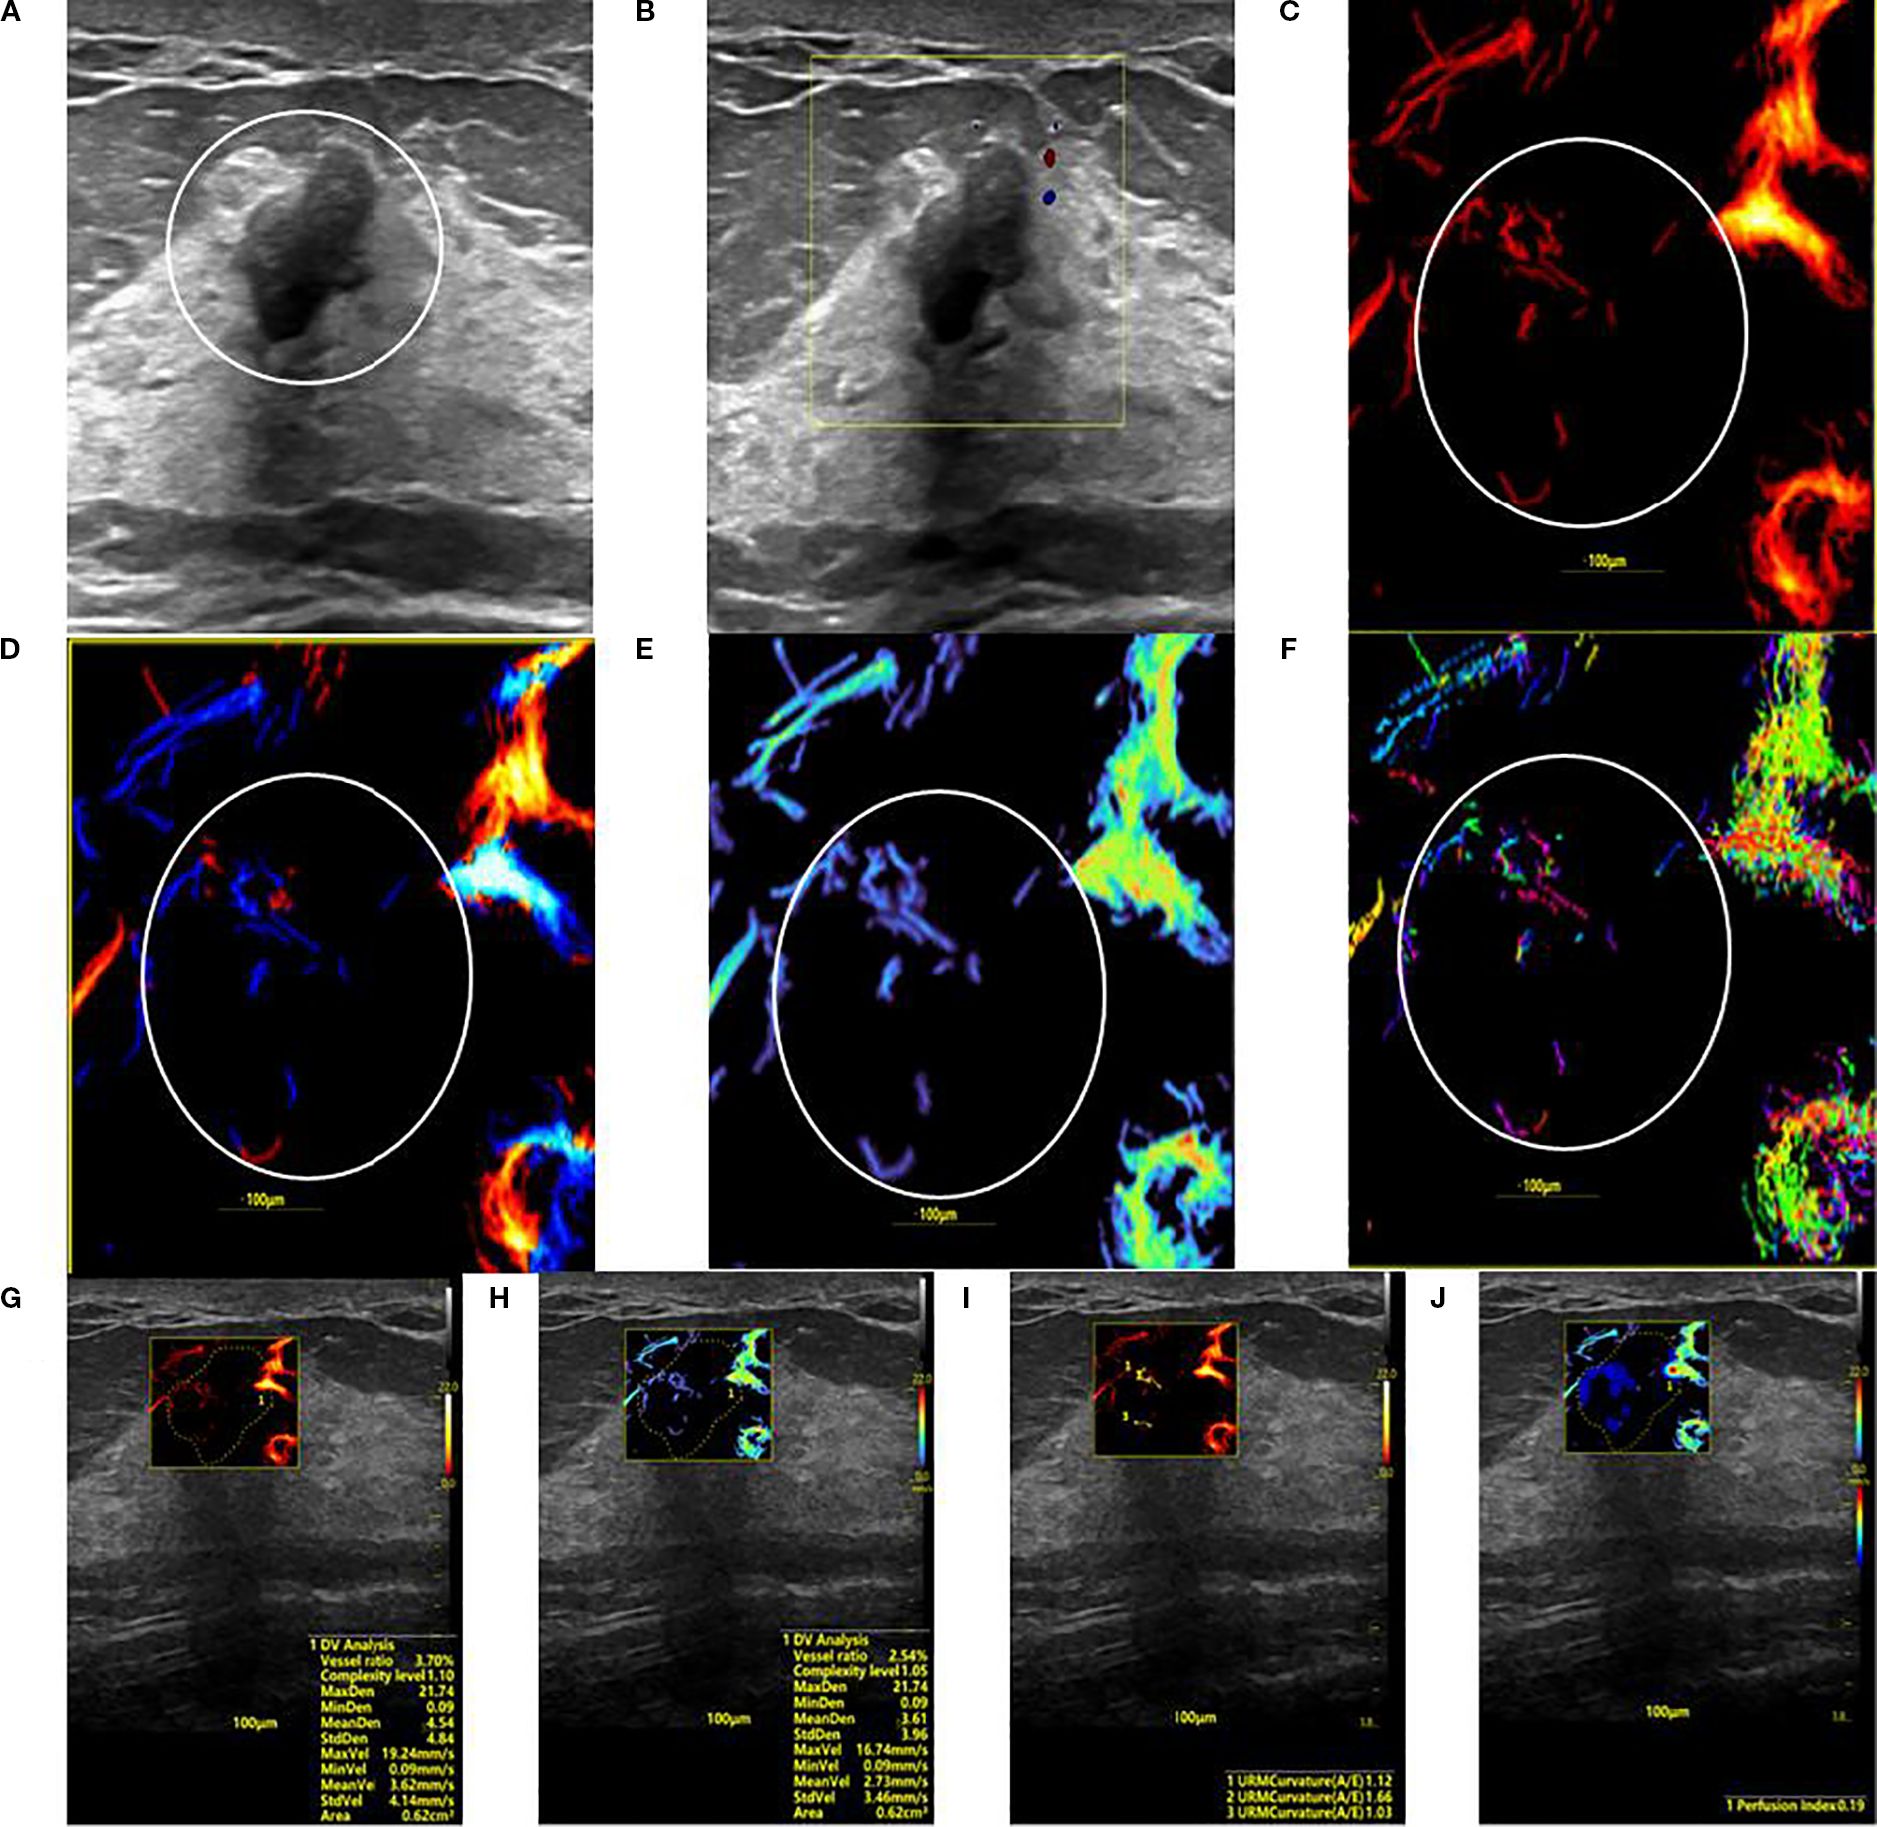

A series of ultrasound images of a hypovascular benign breast lesion. Panel A is a grayscale ultrasound displaying a hypoechoic mass encircled for reference. Panel B is a Super Microvascular Flow (SMF) image. Panels C through F are SRUS parameter maps depicting the lesion's characteristics via Density, Orientation, Velocity, and Angle color maps. Panels G through J are analysis panels showing numerical parameter values overlaid on the corresponding ultrasound images.

Figure 3. SRUS imaging of a hypovascular benign breast lesion: (A) Grayscale ultrasound findings suggest the presence of a hypoechoic mass (8.3 × 5.1 mm) with parallel orientation, well-defined margins, irregular shape, and heterogeneous internal echogenicity. (B) SMF image categorized as Alder grade 0. Density map (C), Orientation map (D), Velocity map (E), and Angle map (F), with the lesion region delineated by circular markers based on SRUS images and associated dynamic sequences. (G–J) SRUS parameter quantification panels: density ratio (2.79%), complexity level (1.05), maximum density (21.74), minimum density (0.09), mean density (3.61), maximum velocity (16.74 mm/s), minimum velocity (0.09 mm/s), mean velocity (2.73 mm/s), curvature A/E (1.12), and Perfusion Index (0.19).